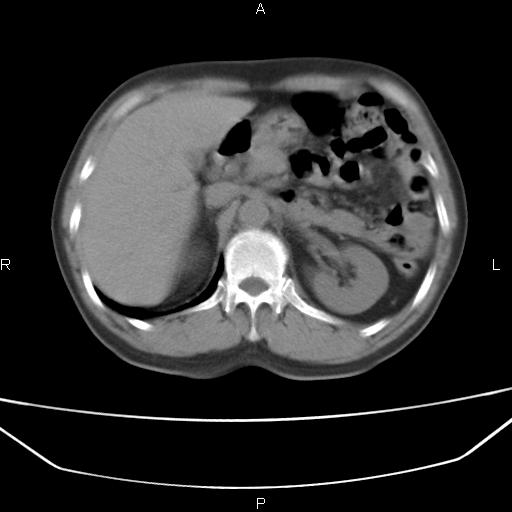

患者,男。50岁。近几日有咳嗽症状,无其他不适,既往病史无,考虑膈疝。请前辈们看看指导指导。

膈膨升,左下肺通气不良,膈肌好像还完整。

考虑左侧膈疝。

左侧膈疝。

符合隔膨升,膈肌较完整。